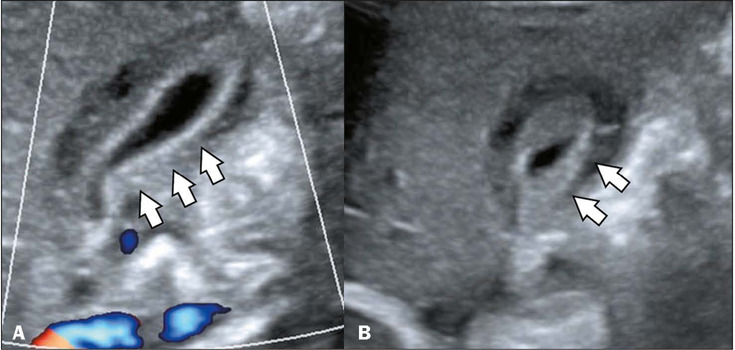

The dengue virus, a member of the family Flaviviridae, is transmitted by Aedes mosquitoes and causes a viral disease known as dengue fever that is prevalent in tropical and subtropical regions. It is estimated that there are 100-400 million new infections every year, with underreporting due to limited surveillance systems. The presentation ranges from asymptomatic to dengue shock syndrome. Brazil is now facing an endemic of dengue, having seen a significant seasonal increase of over 4.5 million in the number of probable cases reported. Imaging exams such as ultrasound, computed tomography, and magnetic resonance imaging are crucial for detecting complications of dengue, aiding in the clinical management and differential diagnosis, especially in severe cases. The aim of this study was to illustrate the radiological findings of dengue, focusing on emergency and critical care settings.